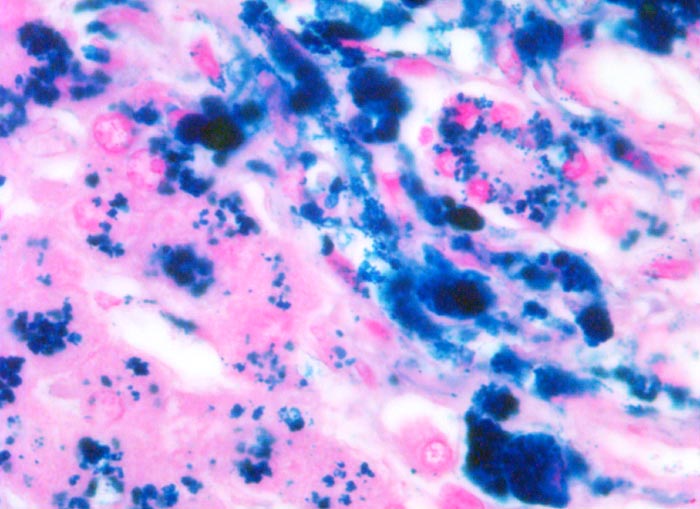

Bei ausgeprägten Eisenablagerungen zeigen parenchymatöse Organe eine Braunverfärbung (> 1521). Die Bestimmung des histologischen hepatischen Eisenindexes nach Deugnier erlaubt eine Abgrenzung der genetisch bedingten Hämochromatose von einer Hämosiderose. Dabei werden Verteilung und Ausmass der Eisenablagerungen berücksichtigt. Bei der Hämochromatose wird das Eisen primär in den periportalen Hepatozyten abgelagert, später auch in Gallengangsepithelien und Gefässendothelien. Bei nicht genetisch bedingter Hämosiderose finden sich die Ablagerungen vor allem in Kupffer Zellen (> 00975).

• Diffuse grobgranuläre Eisenpigmentablagerungen im Zytoplasma von Hepatozyten, Gallengangsepithel und Gefässendothel der Gefässe in den Portalfeldern.

• Gruppen von stark eisenbeladenen Kupffer'schen Sternzellen. Das sollte der Kliniker dem Pathologen mitteilen: